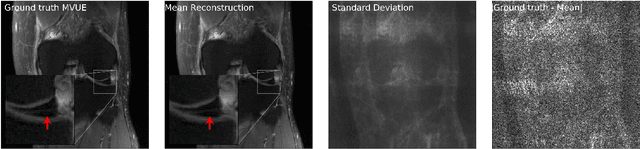

Abstract:Diffusion-based generative models have been used as powerful priors for magnetic resonance imaging (MRI) reconstruction. We present a learning method to optimize sub-sampling patterns for compressed sensing multi-coil MRI that leverages pre-trained diffusion generative models. Crucially, during training we use a single-step reconstruction based on the posterior mean estimate given by the diffusion model and the MRI measurement process. Experiments across varying anatomies, acceleration factors, and pattern types show that sampling operators learned with our method lead to competitive, and in the case of 2D patterns, improved reconstructions compared to baseline patterns. Our method requires as few as five training images to learn effective sampling patterns.

Abstract:Magnetic resonance imaging (MRI) exam protocols consist of multiple contrast-weighted images of the same anatomy to emphasize different tissue properties. Due to the long acquisition times required to collect fully sampled k-space measurements, it is common to only collect a fraction of k-space for some, or all, of the scans and subsequently solve an inverse problem for each contrast to recover the desired image from sub-sampled measurements. Recently, there has been a push to further accelerate MRI exams using data-driven priors, and generative models in particular, to regularize the ill-posed inverse problem of image reconstruction. These methods have shown promising improvements over classical methods. However, many of the approaches neglect the multi-contrast nature of clinical MRI exams and treat each scan as an independent reconstruction. In this work we show that by learning a joint Bayesian prior over multi-contrast data with a score-based generative model we are able to leverage the underlying structure between multi-contrast images and thus improve image reconstruction fidelity over generative models that only reconstruct images of a single contrast.

Abstract:Magnetic Resonance Imaging (MRI) is a powerful medical imaging modality, but unfortunately suffers from long scan times which, aside from increasing operational costs, can lead to image artifacts due to patient motion. Motion during the acquisition leads to inconsistencies in measured data that manifest as blurring and ghosting if unaccounted for in the image reconstruction process. Various deep learning based reconstruction techniques have been proposed which decrease scan time by reducing the number of measurements needed for a high fidelity reconstructed image. Additionally, deep learning has been used to correct motion using end-to-end techniques. This, however, increases susceptibility to distribution shifts at test time (sampling pattern, motion level). In this work we propose a framework for jointly reconstructing highly sub-sampled MRI data while estimating patient motion using score-based generative models. Our method does not make specific assumptions on the sampling trajectory or motion pattern at training time and thus can be flexibly applied to various types of measurement models and patient motion. We demonstrate our framework on retrospectively accelerated 2D brain MRI corrupted by rigid motion.

Abstract:The CSGM framework (Bora-Jalal-Price-Dimakis'17) has shown that deep generative priors can be powerful tools for solving inverse problems. However, to date this framework has been empirically successful only on certain datasets (for example, human faces and MNIST digits), and it is known to perform poorly on out-of-distribution samples. In this paper, we present the first successful application of the CSGM framework on clinical MRI data. We train a generative prior on brain scans from the fastMRI dataset, and show that posterior sampling via Langevin dynamics achieves high quality reconstructions. Furthermore, our experiments and theory show that posterior sampling is robust to changes in the ground-truth distribution and measurement process. Our code and models are available at: \url{https://github.com/utcsilab/csgm-mri-langevin}.